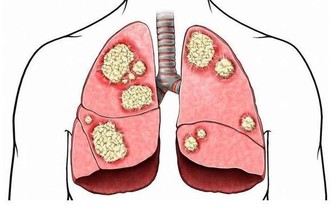

50歲的陳先生因不明原因的咳嗽去醫院就診,誰知道,做完CT檢查,竟發現是肺癌晚期。

這他難以接受甚至是惱怒,因為他每年都體檢,並且都有拍胸片,從未發現異常,為什麼現在一檢查就是肺癌晚期了?

為什麼年年體檢,卻查不出早期肺癌?

類似陳先生一樣遭遇的肺癌患者並不在少數。有人甚至將X光查肺癌稱為“最坑爹的體檢項目”,就連不少醫生也表示,用X光片篩查早期肺癌,確實不靠譜。

雖然X光片在臨床應用廣泛,但因分辨率較低,對於微小以及隱蔽部位的病灶,都不易發現到。用其篩查肺癌漏診率相當高,到用X光能夠查出時,多數已是中晚期了。

而實際上,目前醫學界公認篩查早期肺癌最有效的手段是——低劑量螺旋CT,其發現早期肺癌的敏感度是常規胸片的4~10倍,大大提高肺癌的治愈率和存活率。

但不少人擔心用CT檢查輻射大,會對身體造成傷害,實際上肺癌篩查用的不是CT的常規劑量,其射線量僅為普通CT的1/6,不必過於擔心輻射的問題。

六類高危人群,最好每年查CT

建議50歲左右,尤其是以下肺癌的高發人群,每年最好做一次CT檢查。